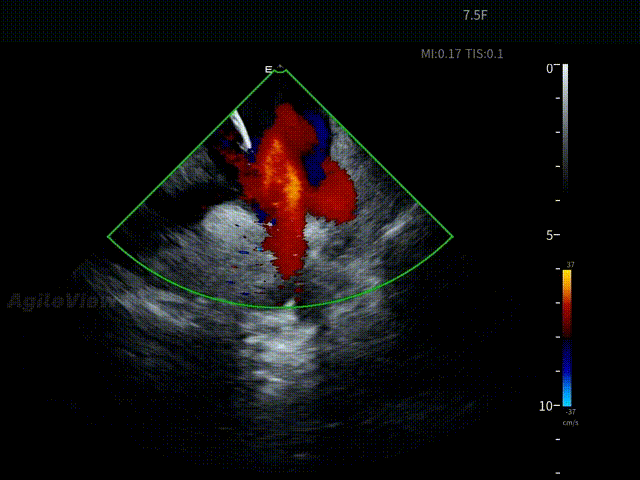

术中,基于AgileView™ 7.5Fr全球最细直径ICE导管的产品优势,周纬教授选择将ICE送入左房,以便更好地进行冷冻球囊的贴靠与位置的判断,在AgileView™ ICE实时影像的指导下, Arctic Front Advance Pro冷冻球囊导管消融导管安全进入左心房,先后完成双侧肺静脉隔离及顶部线隔离, ICE下可见导管贴靠良好,整个消融过程顺利,消融时间仅约25分钟,得益于超声设备清晰的成像质量,在顶部线隔离的时候可借助多普勒模式清晰的观察到球囊与组织的贴靠程度。 整个手术流程在ICE影像的指引下顺利完成,术中患者耐受良好,生命体征保持平稳。

ICE确认LSPV位置——B Mode

ICE确认LSPV位置——C Mode

盐水判断封堵效果——有少量泄露

调整后无泄漏